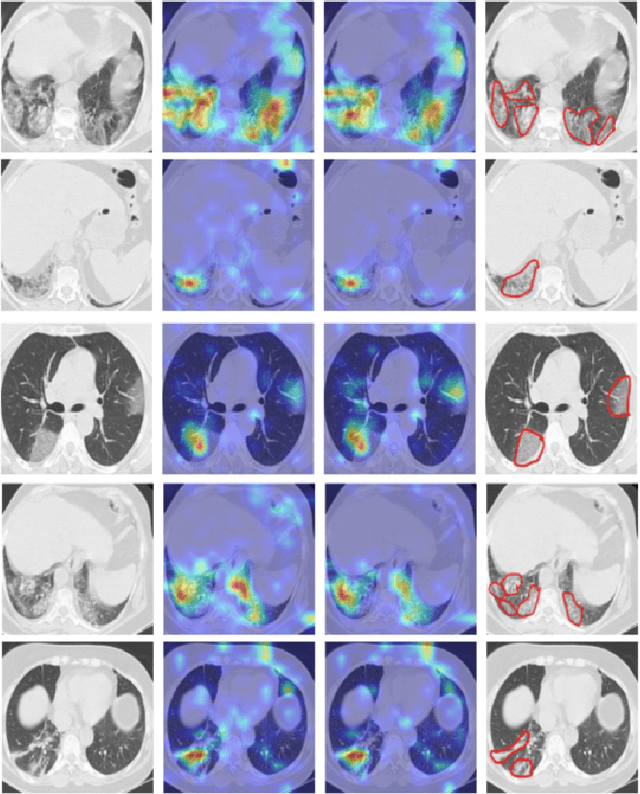

Abstract:The novel corona-virus disease (COVID-19) pandemic has caused a major outbreak in more than 200 countries around the world, leading to a severe impact on the health and life of many people globally. As of Aug 25th of 2020, more than 20 million people are infected, and more than 800,000 death are reported. Computed Tomography (CT) images can be used as a as an alternative to the time-consuming "reverse transcription polymerase chain reaction (RT-PCR)" test, to detect COVID-19. In this work we developed a deep learning framework to predict COVID-19 from CT images. We propose to use an attentional convolution network, which can focus on the infected areas of chest, enabling it to perform a more accurate prediction. We trained our model on a dataset of more than 2000 CT images, and report its performance in terms of various popular metrics, such as sensitivity, specificity, area under the curve, and also precision-recall curve, and achieve very promising results. We also provide a visualization of the attention maps of the model for several test images, and show that our model is attending to the infected regions as intended. In addition to developing a machine learning modeling framework, we also provide the manual annotation of the potentionally infected regions of chest, with the help of a board-certified radiologist, and make that publicly available for other researchers.